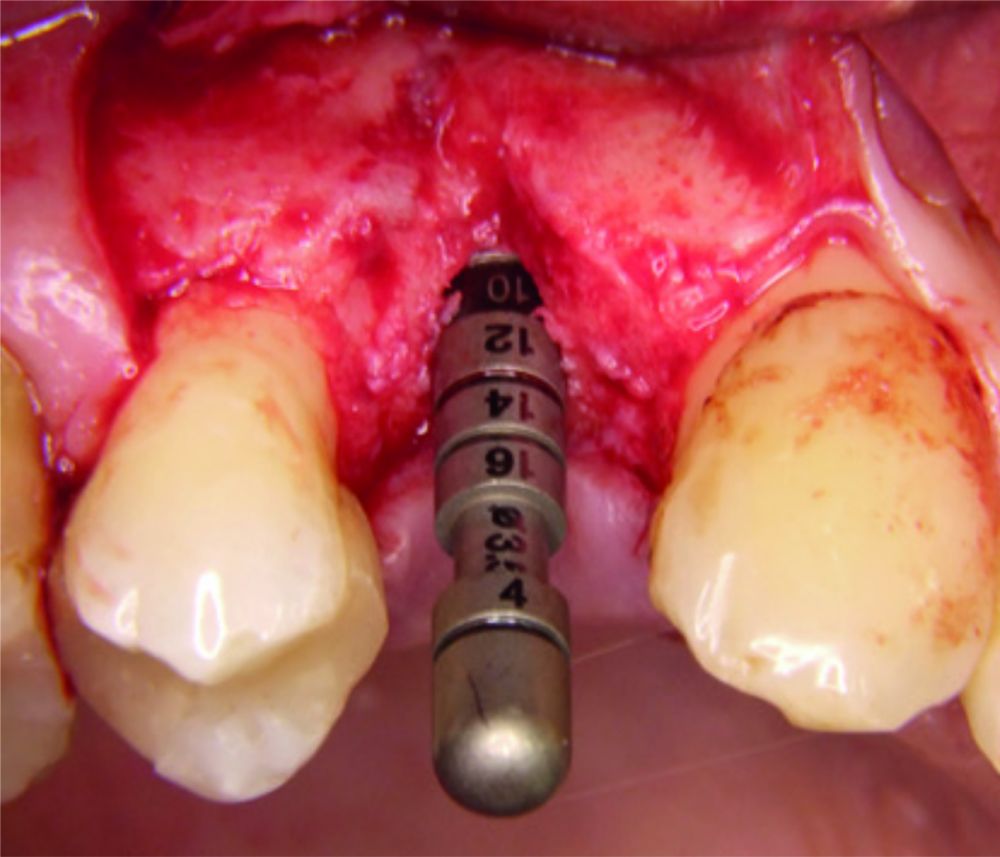

Die gesteuerte Knochenregeneration (GBR) ist die am besten dokumentierte Methode zur Augmentation von Knochen bei lokalisierten Alveolarkammdefekten.1

Wesentliche kritische Parameter sind u.a. die Stabilisierung des Wundraums und ein umgehender, ungestörter Gefäßanschluss des Augmentats.

Aufgrund der benachteiligten mechanischen Lagestabilität der Knochenpartikel kann es zu einem Kollaps des augmentierten Defektvolumens kommen.5-9 Durch Mischung von Knochenpartikeln mit Hyaluronsäure können die Lagestabilität verbessert sowie Heilungsprozesse beschleunigt werden.

Dies konnte in einer klinischen Vergleichsstudie gezeigt werden. Die Patienten mit ausgeprägten horizontalen Kieferkammdefekten wurden mit einem klassischen GBR-Ansatz (Kombination eines langsam resorbierenden bovinen Knochenersatzmaterial und einer nativen Kollagenmembran) behandelt. In der Testgruppe wurde vor der Augmentation sowohl das Knochenersatzmaterial als auch die Membran mit xHyA vermischt. Nach 6 Monaten konnte in der xHyA-Gruppe ein signifikant höherer Zugewinn an Kieferkammbreite verzeichnet werden (7,7mm vs. 4,4mm).26